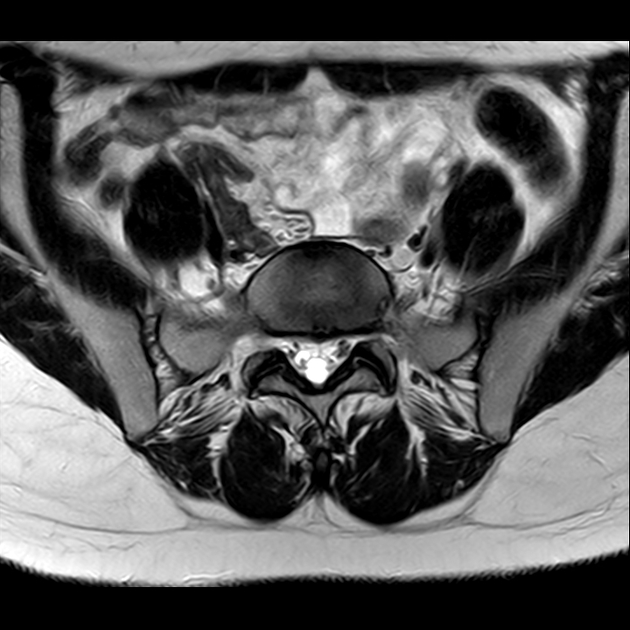

磁共振检查:

T2